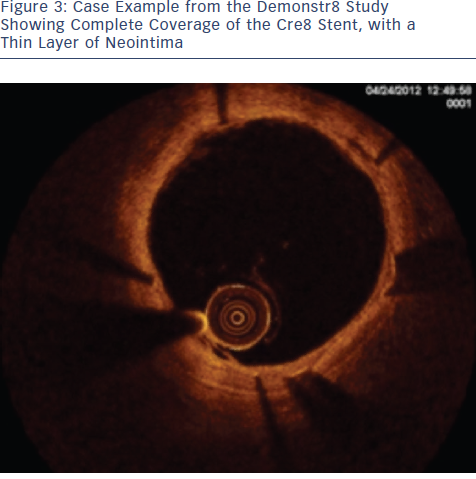

The study recruited 38 patients with ischaemic myocardial symptoms related to de novo lesions in native coronary arteries, in six European sites.5 The primary endpoint was the percentage of sections with a Ratio of Uncovered to Total Stent Struts per Cross Section (RUTTS) score < 30 % at three-month non-inferior to Vision Multilink percentage of sections with RUTTS score < 30 % at one month. The 35 patients suitable for analysis have led to the evaluation of 17,000 struts in 2000 analysed sections. RUTTS scores <30 % were seen in 99.78 % of patients receiving a Cre8 DES and 99.55 % of patients receiving a BMS. In terms of secondary endpoints, OCT analysis showed superiority of the Cre8 group in terms of mean neoimtima thickness at months one and three (0.08±0.03 mm in Cre8 group vs 0.18±0.10 mm in BMS group; p<0.0001; see Figure 3). In conclusion, results to date from this study show that Cre8 has an excellent safety profile, with low RUTTS scores and low neointima thickness.